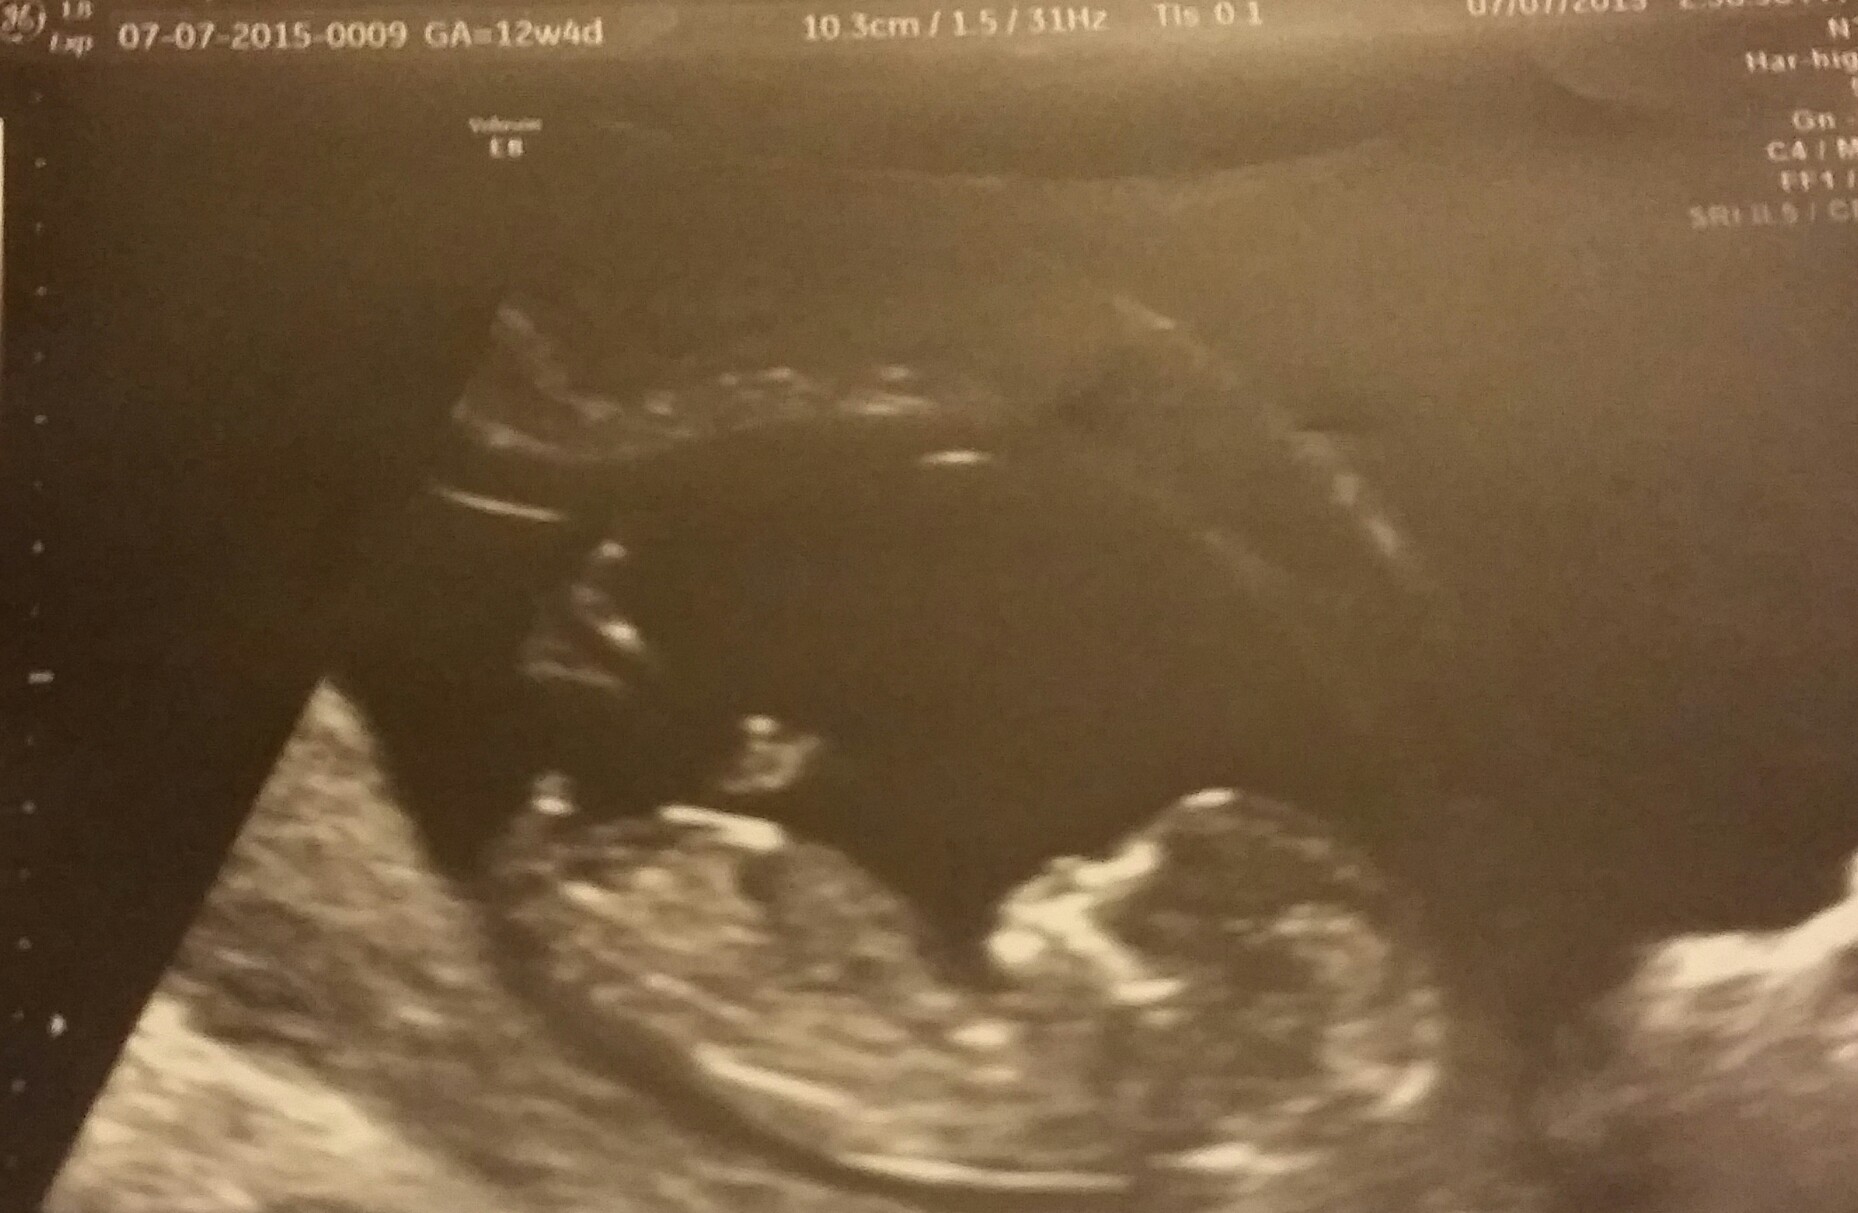

Woohoo!!! Based on my LMP I'm 12w4d and measured exactly 12w4d. HB was 140 and all when well with the NT scan. Big sighs of relief for this PGAL mama. Xo